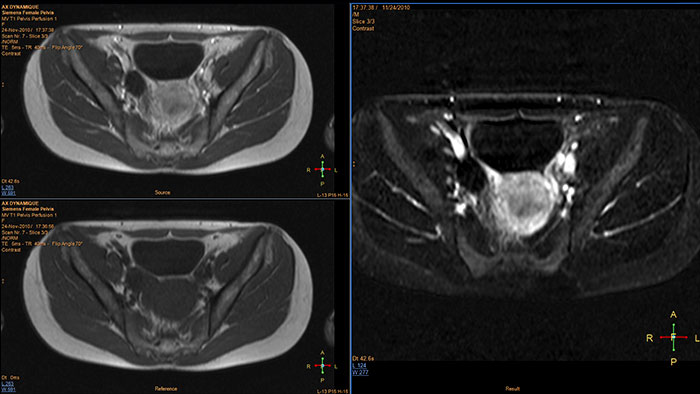

Support in assessing lesions by reviewing blood supply characteristics

Designed to evaluate time intensity curves of a T1 signal enhancement series. The application produces measurements including relative enhancement, maximum enhancement, time to peak (TTP), and wash-in/wash-out rates.